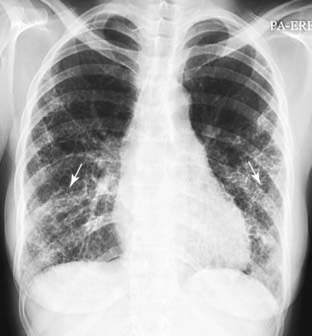

Figure 3-13 Rheumatoid lung.

Prominent markings at both lung bases have a predominantly reticular appearance (solid white arrows). Bibasilar interstitial disease can be found in numerous diseases including bronchiectasis, asbestosis, desquamative interstitial pneumonia (DIP), scleroderma, and sickle cell disease. This patient was known to have rheumatoid arthritis. Pleural effusion is the most common manifestation of rheumatoid lung disease, and pulmonary fibrosis, usually diffuse but more prominent at the bases, is second most common.